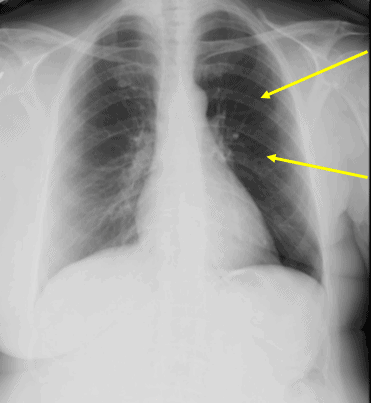

No acute lung infiltrates; left lung hyperlucent postmastectomy.

Learnings/What to Look for

- Common causes include:

- Compensatory distention of adjacent lobe or lung

- Contralateral increased density (eg, chest wall hemihypertrophy; pleural effusion)

- Emphysema, bullous or diffuse; large bulla

- Air trapping (eg, bronchial foreign body, stricture, mucus plug or neoplasm)

- Pectoral muscle absence, congenital (eg, Poland syndrome) or surgical (mastectomy) or atrophy (eg, polio)

- Pneumothorax

- Scoliosis

- Technical factors: positioning (eg, patient rotation); grid cutoff

Pearls for Urgent Care Management and Considerations for Transfer

- Consult the history for prior surgery or infections

- Assess the soft tissues to exclude mastectomy (as in this patient)